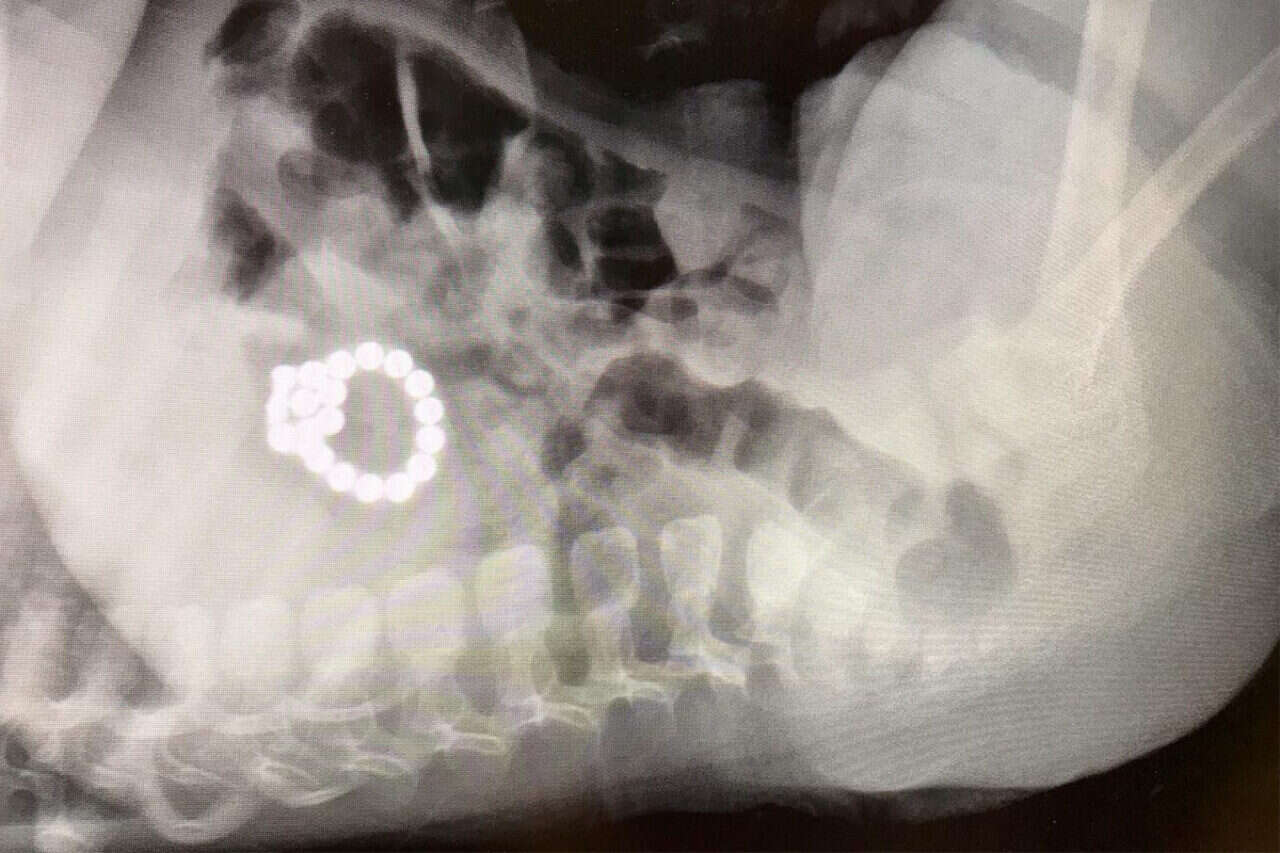

המגנטים שנמצאו בצילום , צילום: דוברות הדסה

בניתוח רגיש השבוע בבית חולים הדסה שלפו הרופאים 19 מגנטים, שהסתתרו בבטנו של תינוק כבן שנה. הפעוט הובהל לבית חולים הדסה הר הצופים בעקבות מחלת חום קצרה וצמרמורות. רופא הילדים בבית החולים, שבדק את התינוק, חשד כי מדובר בנסיבות יותר מאתגרות והפנה לצילום חזה שם התגלו, באופן מפתיע ביותר המגנטים עגולים שהתינוק בלע.

ההורים לא ידעו על כך ואמרו שראו ששיחק במגנטים כשבועיים-שלושה קודם לכן. מכאן החל הליך מורכב של מאמצים רבים להצילו. ד״ר זאב דוידוביץ, רופא גסטרו ילדים בהדסה הר הצופים, הצליח לשלוף 12 מהמגנטים בהליך רגיש וייחודי, בעזרת רשת מיוחדת. "בצילום התגלו עצמים זרים בבטן בצורת כדורים- מצב מסוכן ביותר, שעלול ליצור חסימה או ניקוב של המעי ולהוביל לסכנת חיים", סיפר ד"ר דוידוביץ'.